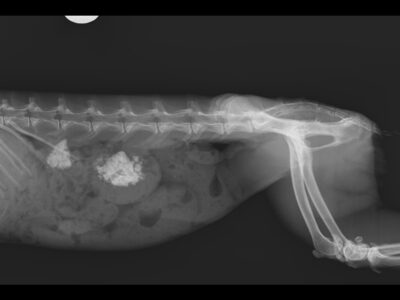

Radiografies de petits mamífers exòtics

En aquesta entrada podrem observar proves d'imatge realitzades a petits mamífers exòtics com a conills, fures i cobais.